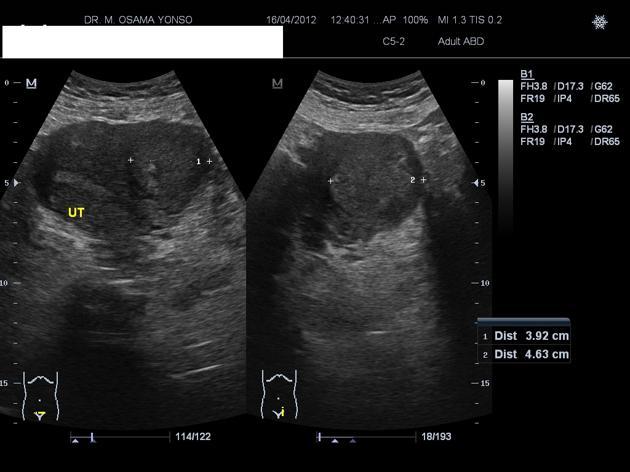

Diagnosis?

Cause?

Adenomyosis.

Focal or diffuse invasion of endometrial tissue into the myometrium. Look for asymmetric thickening of the junctional zone (>12 mm), 50% have small cystic lesions in the myometrium. The endometrium looks normal.

Note- because the basal layer of the endometrium invades the myometrium, it does not show changes with the menstrual cycle.